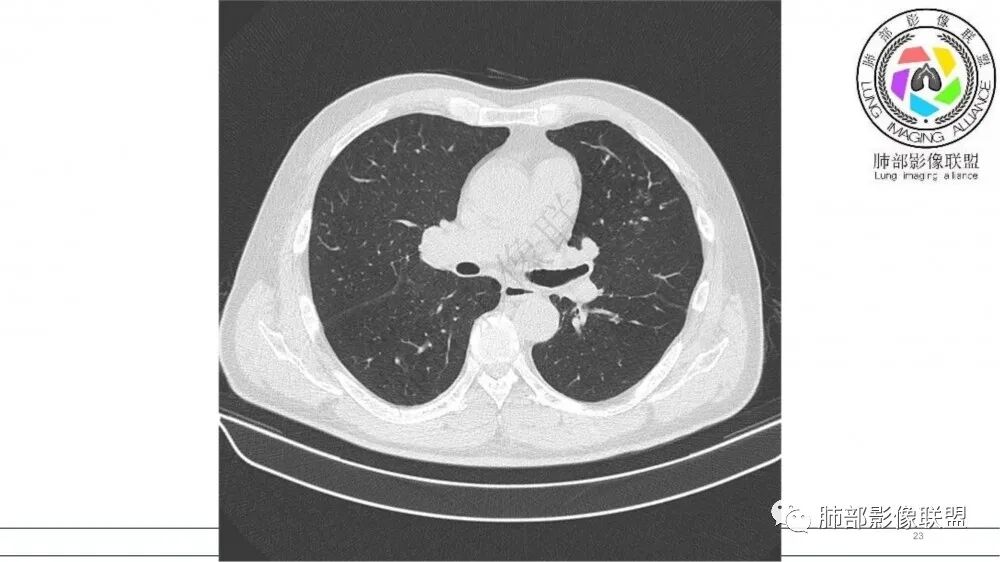

左肺上叶前段支气管杵状指样扩张,内见实性组织阻塞性,并强化明显,边缘饱满,周边多发小斑点影,小花小草征,老年男性,长期吸烟史,方向恶性,首选支气管内浸润鳞Ca可能性大。

男,70岁,吸烟史,咳嗽,胸闷憋气一个月,左肺上叶不规则形软组织密度影,病灶沿支气管走形,周围见粟粒及棉絮样稍高密度影,增强扫描病灶内见少许坏死,考虑鳞癌可能,鉴别结核。

老年男性,肺气肿,吸烟史,左肺上支气管腔内铸型高密度影,呈指套状,远端多发树芽,增强不均匀强化,考虑鳞癌,鉴别小细胞癌

B3指套征,常规不是鳞癌就是ABPA,有强化丶血管造影征,倾向于鳞癌

左肺上叶尖后段支气管近端截断,远端见高密度铸型,远侧见阻塞性改变,老年男性,吸烟史,考虑恶性,鳞癌。ABPA代排

老年男性,长期吸烟史。左上肺前段沿支气管走形的指套样病变,增强可见病灶强化(排除结核、ABPA(也无气喘症状)),远端多发点状高密度影。考虑恶性肿瘤,鳞癌可能性大。

指套征明确吧

指套征,扩张支气管内软组织强化,远侧肺野阻塞性炎,纵隔、左肺门肿大淋巴结;老年男性,吸烟,考虑鳞癌,鉴别小

老年吸烟男性,尖前段支气管内塑形生长,增粗蠕虫样,没有肺不张(排除鳞癌?),远端少许阻塞肺炎,增强低强化,锁定小

老年男性,吸烟,指套征,蠕虫征,阻塞性炎症不严重。可见血管穿行,密度均匀,轻度强化,首先考虑小细胞肺癌。鉴别鳞

指套征:是影像征象,胸部平片表现为手指状密度增高影,以肺门为中心呈放射状分布,CT显示扩张支气管内低密度黏液栓形成或实性病变,呈管状、树枝状或卵圆形密度增高影;支气管扩张伴近端梗阻时,扩张支气管内部黏液分泌物不能排出而形成。可以伴随远端空气潴留征、阻塞性炎症。

研究报道,中心型 SCLC 经 CT 扫描后通常支气管表现为鼠尾样狭窄,肺门或纵隔肿块明显,由于肿块沿管壁生长表现为顺延支气管形态的不规则形状。病灶相对特征性影像学表现比如鸭蹼状、腊肠状、葫芦状及葡萄状改变,可以出现血管包埋,很少有空洞、空泡,较少引发肺不张,阻塞性炎症成都较轻。与一般肺癌比较,恶性程度高,侵袭力强、病灶很小就容易远处转移!Herzberg 等[19]研究指出,20%以上 SCLC 倍增时间短,预后不良。